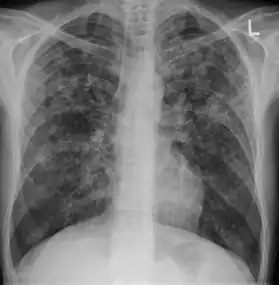

Chest X ray showing miliary tuberculosis

Miliary tuberculosis is a form of tuberculosis that is characterized by a wide dissemination into the human body and by the tiny size of the lesions (1–5 mm). Its name comes from a distinctive pattern seen on a chest radiograph of many tiny spots distributed throughout the lung fields with the appearance similar to millet seeds—thus the term "miliary" tuberculosis. Miliary TB may infect any number of organs, including the lungs, liver, and spleen.[2] Miliary tuberculosis is present in about 2% of all reported cases of tuberculosis and accounts for up to 20% of all extra-pulmonary tuberculosis cases.[3]

Testing for miliary tuberculosis is conducted in a similar manner as for other forms of tuberculosis, although a number of tests must be conducted on a patient to confirm diagnosis.[4] Tests include chest x-ray, sputum culture, bronchoscopy, open lung biopsy, head CT/MRI, blood cultures, fundoscopy, and electrocardiography.[10] The tuberculosis (TB) blood test, also called an Interferon Gamma Release Assay or IGRA, is a way to diagnose latent TB. A variety of neurological complications have been noted in miliary tuberculosis patients—tuberculous meningitis and cerebral tuberculomas being the most frequent. However, a majority of patients improve following antituberculous treatment. Rarely lymphangitic spread of lung cancer could mimic miliary pattern of tuberculosis on regular chest X-ray. [15]